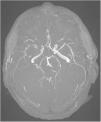

Vasculitis primaria del sistema nervioso central. Una enfermedad rara con alta mortalidad

Primary central nervous system vasculitis. A rare disease with high mortality